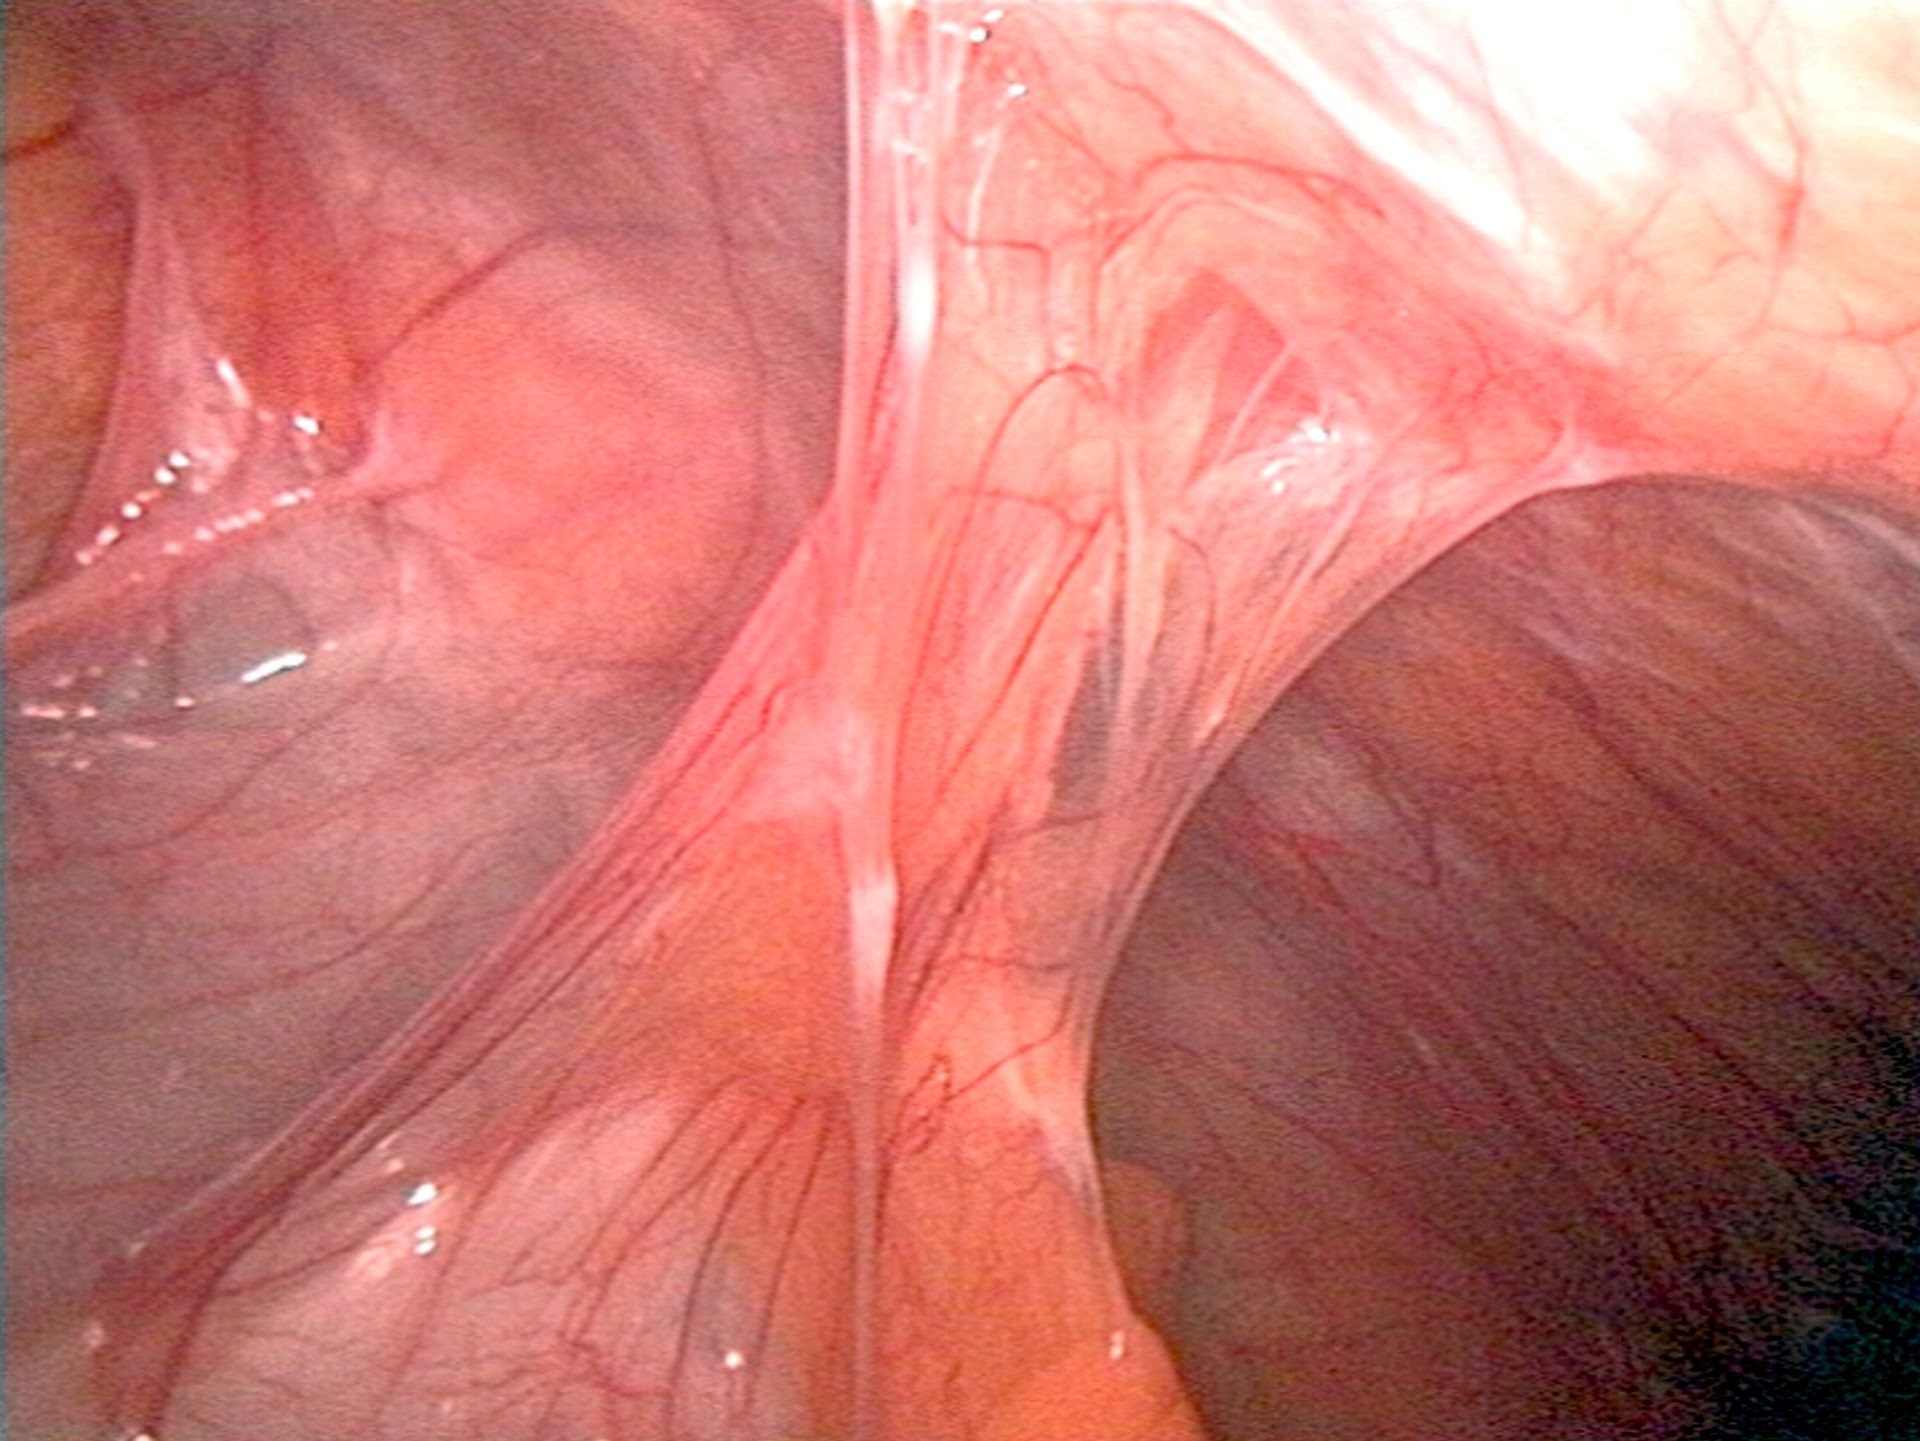

BRIDAS E ADERÊNCIAS INTESTINAIS.

Visão histórica de um problema que se mantém atual. Bridas e aderências intra abdominais são lesões já referenciadas nos papiros do antigo Egito. Bem conhecida nos primórdios da patologia no contexto da tuberculose ou outra doença infamatória peritoneal, torna-se comum depois do advento da cirurgia abdominal na segunda metade do século XIX, pela obstrução intestinal que estas aderências pós-operatórias criam. É uma patologia que ainda hoje mantém importante morbilidade. O autor revê a evolução histórica desta doença e apresenta uma imagem dos primórdios do registo gráfico desta patologia.

No século XX a maior parte de tipos de materiais atualmente em utilização ou em desenvolvimento foram propostos para prevenção das aderências: líquidos, geles, barreiras, drogas fibrinolíticas, polímeros hidrossolúveis e polímeros orgânicos. No entanto após um período inicial de algum entusiasmo a prática não consagrou a sua utilização. E voltamos mesmo assumir uma referência prévia com o conceito “ot the intestines”. De fato, se mantivermos os intestinos e órgãos intra-abdominais com uma solução que os mantenha com movimento, não permitimos a junção de duas superfícies peritoneais lesadas que possam levar à formação de bridas. Para este motivo vem sendo proposto o uso de solução utilizada na diálise que se mantém no abdômen por um período de cerca de 5 dias, antes da sua reabsorção.